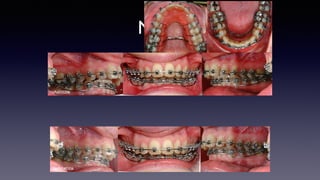

•Lingual button + elastomeric

chain to help derotation

•Mx + Md: .016 supercable™

ClPe120612

At 15 weeks

•Md: 16x22 cnt

•Mx: ∆EC. .016 sc™

ClPe240912